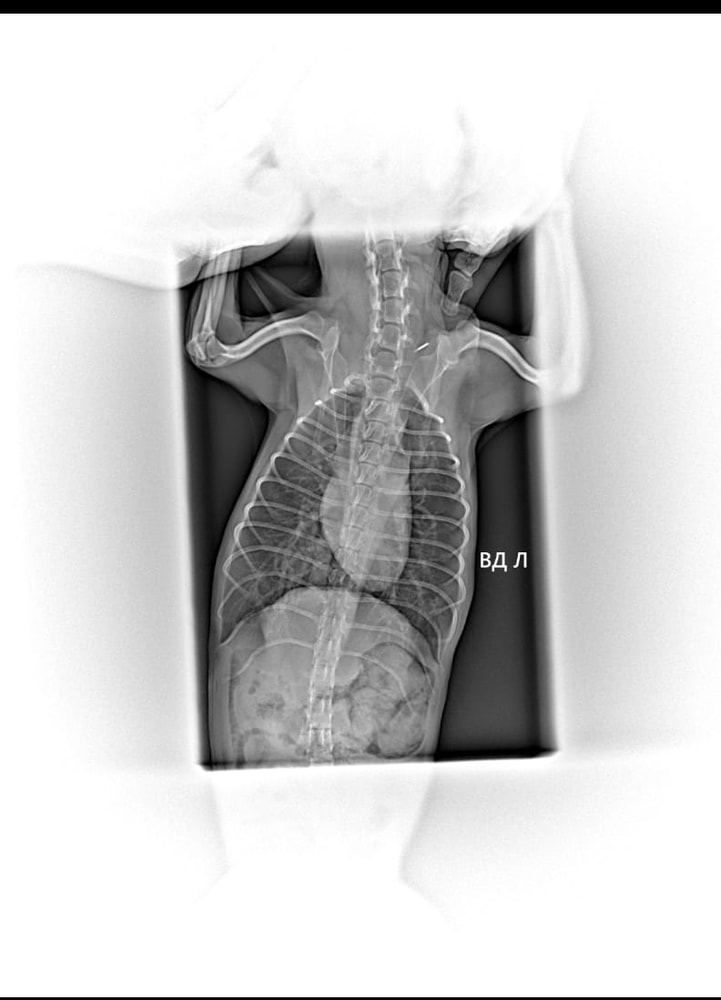

Похоже на пневмонию?

Собака дышит со свистом, иногда как будто втягивает сопли, больше никаких признаков нет. Аппетит нормальный, вялости нет, температуры тоже. Сопли не текут, кашля нет. Сходили к ветеринару, сказал, что хрипов нет, но по рентгену поставили диагноз ринит, трахеит, бронхопневмония. Антибиотику пошел 7-й день, так же капаю в нос и пою отхаркивающим. Улучшений не вижу, ухудшение тоже. Кто разбирается, посмотрите, пожалуйста, снимки 🙏